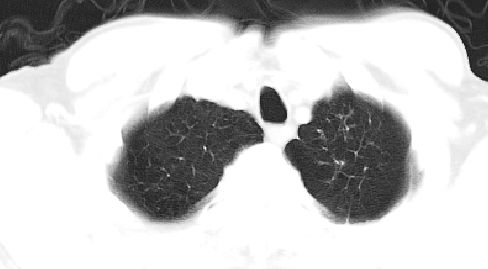

标题: CT10147:男、55岁,咯血10天,有结核病史。 [打印本页]

标题: CT10147:男、55岁,咯血10天,有结核病史。

左上肺见软组织密度肿块影,边缘呈分叶状,可见毛刺,肺门纵隔淋巴结增大,考虑左侧周围型肺癌。左上肺陈旧性结核纤并维化。

双肺上叶结核